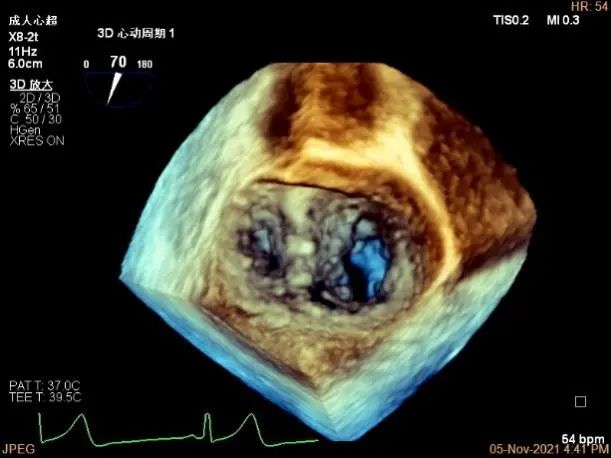

3D MV View:A2/A1区脱垂

3D-color MV view:血流主要来源于A2区,少部分来源于A1区

3D视图下观察二尖瓣双孔形态

3D-color:残余少量返流